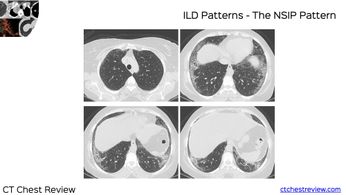

Case 30: The Story of the Samosa-Wrap Worker Paid Members Public

51-years old man with dyspnea, gradually progressive, working as a samosa-wrap worker in Dharavi